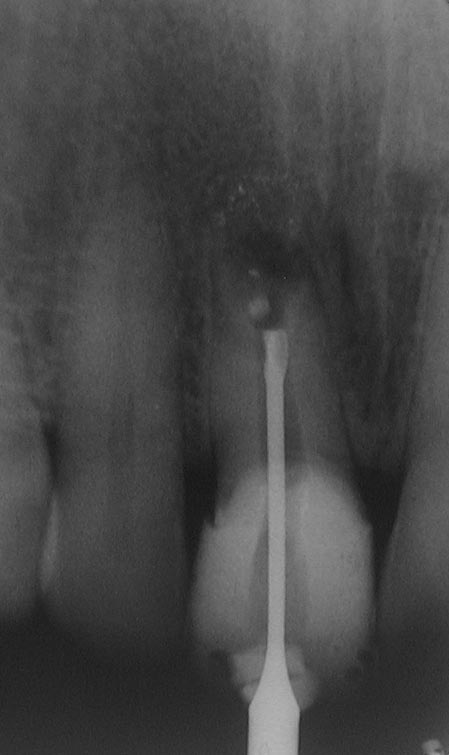

BB-1-7

(Miss)Erfolg des Tages